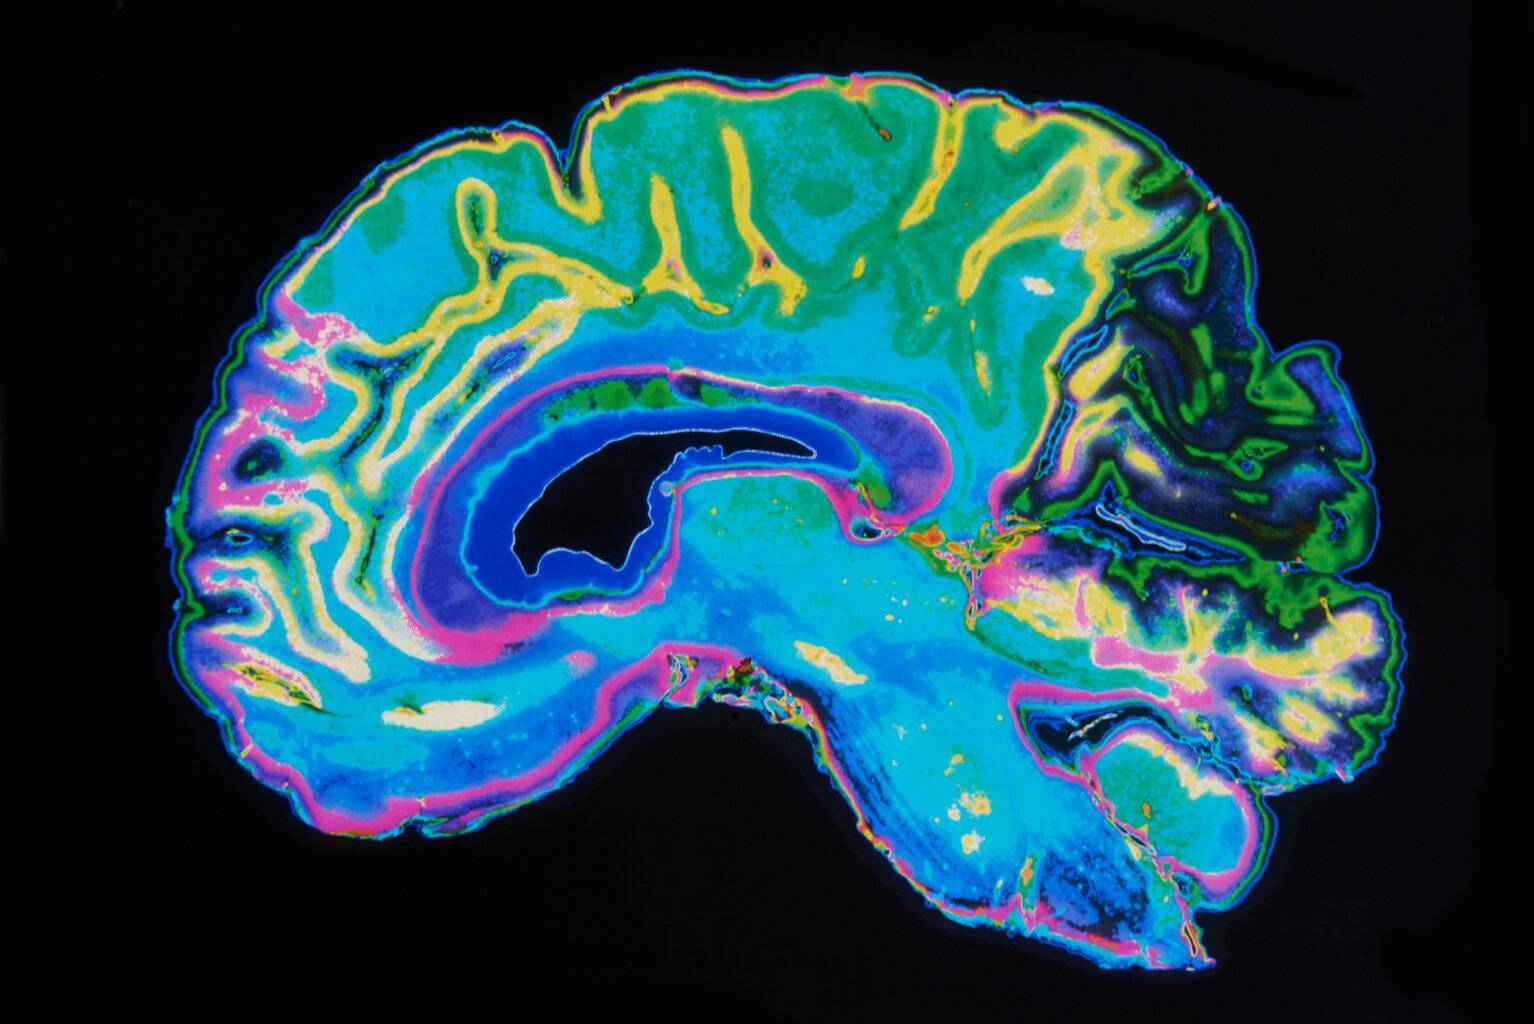

Außerdem wird in der Regel Blut abgenommen. Es gibt zwar keinen Demenzmarker, allerdings lassen sich verschiedene Ursachen sekundärer Demenzen mittels Laboruntersuchungen ausschließen. Zu diesem Zweck kann zusätzlich eine bildgebende Diagnostik des Gehirns mittels MRT oder CT erfolgen.